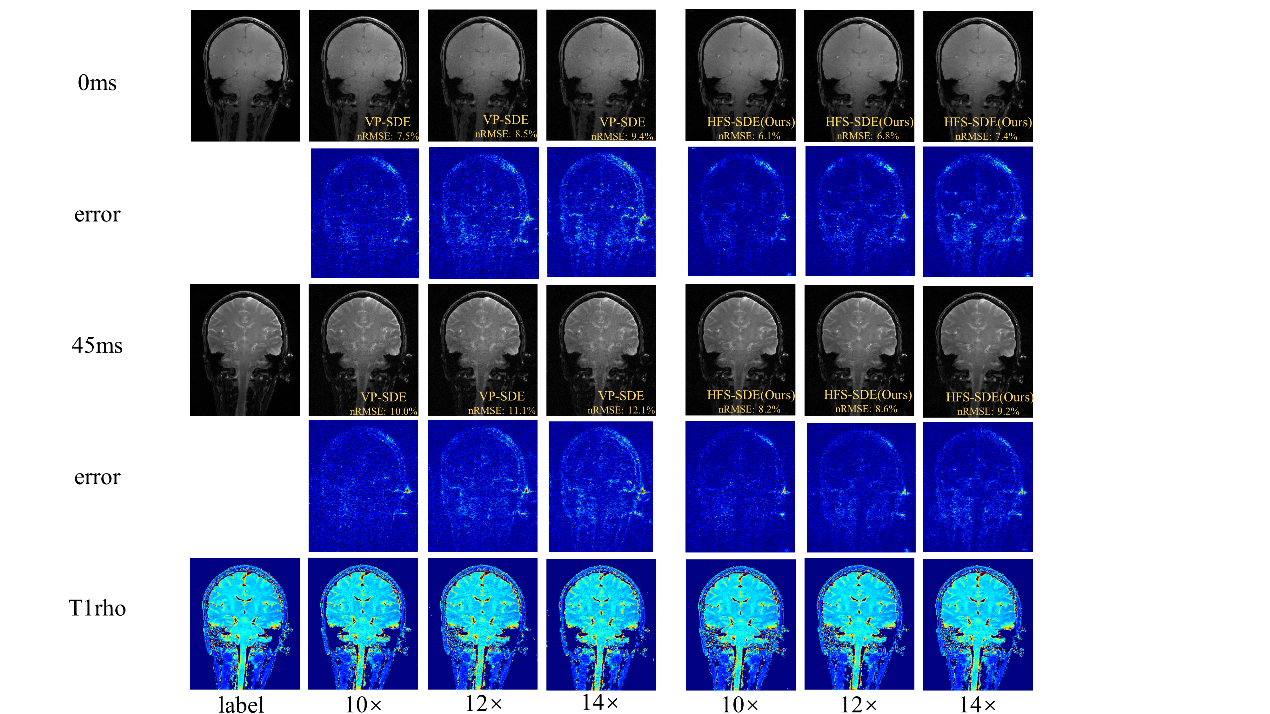

在超高场功能磁共振T1ρ弛豫定量成像方面,团队首次在5.0 T磁共振平台上测试了大脑T1ρ成像的可行性,并比较了使用3.0 T5.0 T扫描仪所得的T1ρ值。实验结果表明,5.0T下取得了信噪比更高的T1ρ加权图像。在高分辨率成像中,5.0T的信噪比优势更明显。该成果发表在Frontiers in Physics(2022,10:1016932)。团队还提出一种用于基于扩散的MR重建方法——HFS-SDE,并将这种新方法应用于MR T1ρ映射,实现14的高加速度,相对于VP-SDE的高速倍数下没有显示伪影,nRMSE值明显优于VP-SDE,并且图像的高频细节得到了更好的重建,该成果“Diffusion generative prior-based highly accelerated MR T1ρ mapping2023 ISMRM会议收录为Power Pitch

团队提出的HFS-SDE方法不仅提高了扩散模型的稳定性,并在5T时实现了T1ρ定量成像的高加速,而且更准确地恢复MR图像中的高频细节。